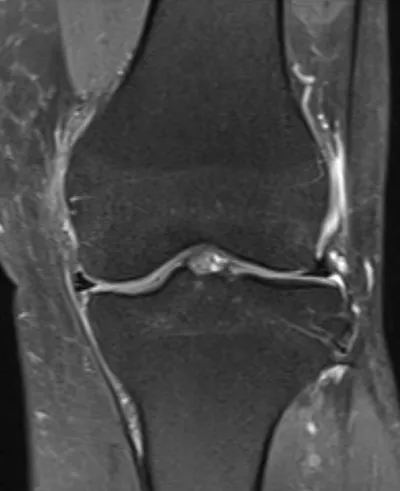

This collection contains 2 radiology images related to bursitis, including various imaging modalities such as X-rays, MRIs, CT scans, and ultrasound images commonly used in medical diagnosis and education.